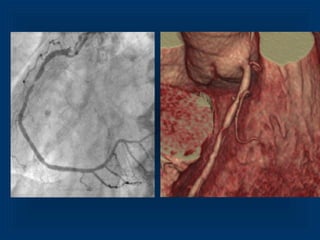

Maximum Intensity Projection RCA 3D VRT LCX and RCA

Maximum Intensity ProjectionRCA 3D VRT LCX and RCA